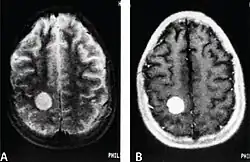

CNS metastases are diagnosed through imaging techniques that produce detailed images of the inside of the body, including parts such as the bones, organs, muscles, and nerves.[13] Magnetic resonance imaging (MRI) and computed tomography (CT) are two representative imaging procedures for this purpose.[12]

MRI scans use strong magnetic fields and radio waves to create an image, while CT scans use X-rays. MRI scans produce more detailed images of bodily structures, particularly soft tissues including the brain,[13] and are better at detecting CNS metastases than CT scans. However, CT scans are sometimes used for the initial imaging modality due to their lower cost and efficiency in screening for multiple conditions.[14]